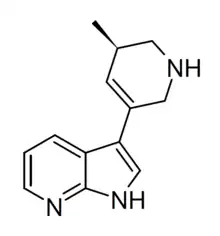

Related compounds

A number of related compounds are known, with a similar structure but having the indole core flipped and/or replaced with related cores such as indoline, indazole, benzothiophene, or benzofuran. These similarly are primarily active as agonists at the 5-HT2 family of serotonin receptors, with applications in the treatment of glaucoma, cluster headaches or as anorectics.

(R)-69 | 3-[(5R)-5-methyl-1,2,5,6-tetrahydropyridin-3-yl]-1H-pyrrolo[2,3-b]pyridine | |